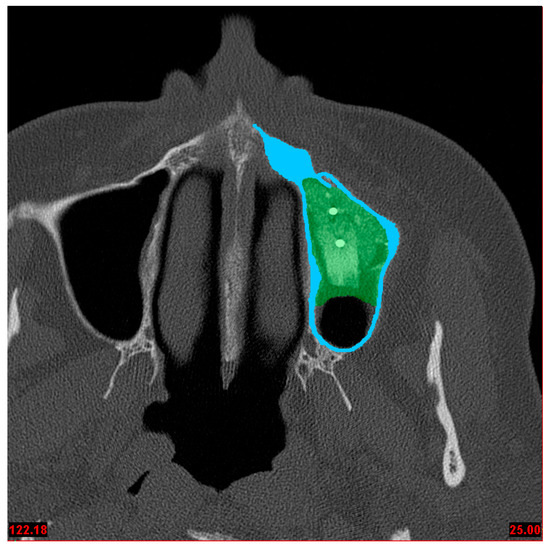

Figure 3.

M2_c model—left: Compact bone, the implant and the bone graft in middle position; right: Compact bone with augmentation.